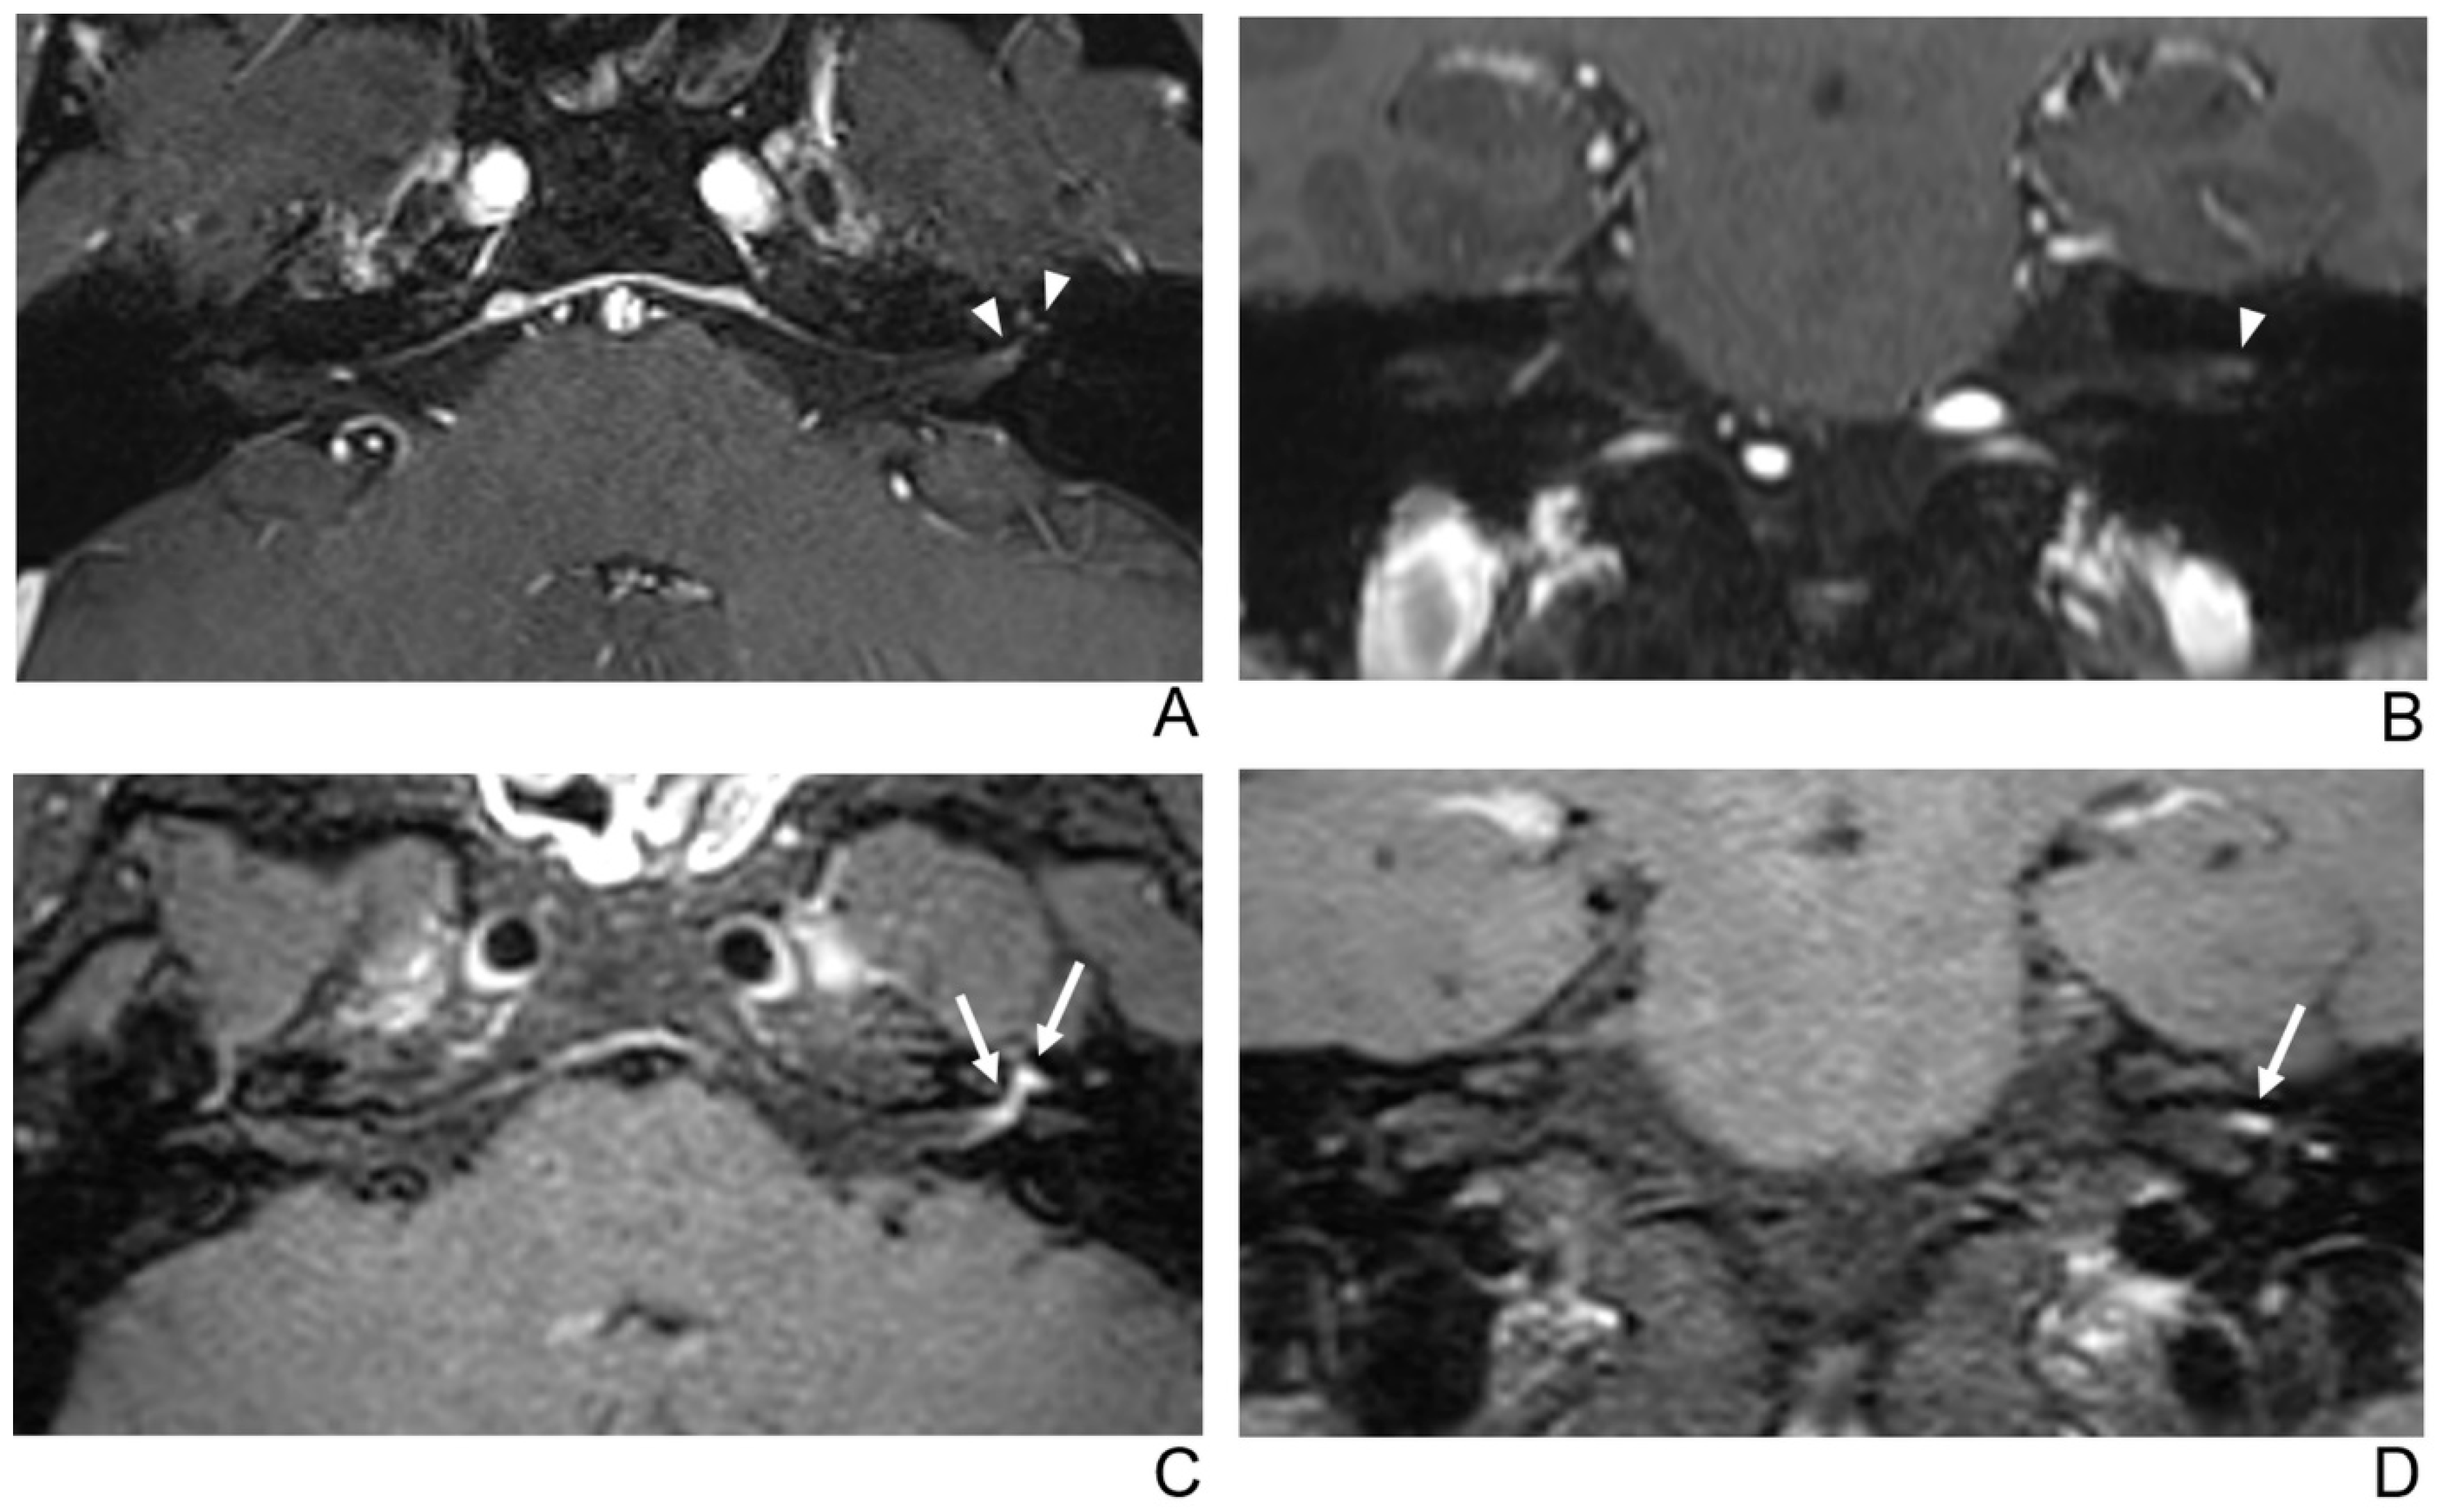

Figure 2.

A 39-year-old male patient with left facial neuritis. (A–D) Paired axial and coronal CE-GRE (A,B) and T1 BB-FSE (C,D) images of the same patient. The left distal canalicular segment of the facial nerve showed asymmetric, intense enhancement in the axial (A) and coronal (B) CE-GRE images (arrowheads). In contrast, the labyrinthine segment showed no definite enhancement, and the anterior genu segment showed moderate degree enhancement and was interpreted by reviewers 1 and 2 as left facial neuritis (2, diagnostic confidence; 3, 0, and 2, visual grades for contrast enhancement (CE) in the canalicular, labyrinthine, and anterior genu segments, respectively). The left facial nerve shows asymmetric intense enhancement in the canalicular, labyrinthine, and anterior genu segments in the axial (C) and coronal (D) T1 BB-FSE images (arrows); it was evaluated by reviewers 1 and 2 as left facial neuritis (2, diagnostic confidence; 3, 2, and 3, visual grades for CE in the canalicular, labyrinthine, and anterior genu segments, respectively). Compared to the CE-GRE images shown earlier, in the T1 BB-FSE image, it can be seen that the contrast-enhanced area in each segment of the facial nerve is longer and wider.